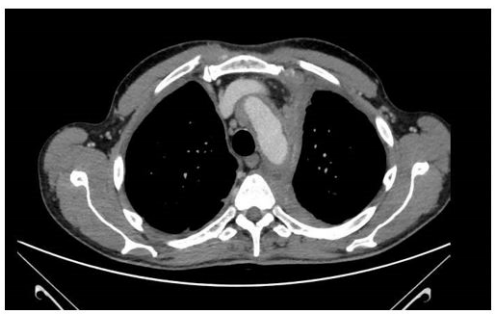

Chest X-ray showed interstitial thickening of lung, ilo-perilary congestion and bilateral pleural effusion major on the left. The findings were investigated with contrast enhanced CT of chest and abdomen, which documented the presence of solid tissue infiltrating both pleurae, mediastinal fatty tissue and pericardium, perirenal fascia and perihepatic area, and surrounding the aortic arch, the proximal tract of the epiaortic vessels.

Cardiac and mediastinal involvement was investigated by cardiac MRI. which showed elevated Tl myocardial values, suggestive for infiltrative/storage disease. A solid tissue diffusely infiltrated pericardium, especially in the right posterolateral position, and the atrioventricular right sulcus.

In fact, the imaging examinations performed during the last hospitalization showed a multiorgan involvement, in. duding coated aorta, hairy kidney. long bone thickening lesions, that lead us to consider a systemic disease. All that findings were consistent with the diagnosis of ECD, which was further corrob- orated by the histological finding of foamy histiocytes containing lipids reactive for CD68.